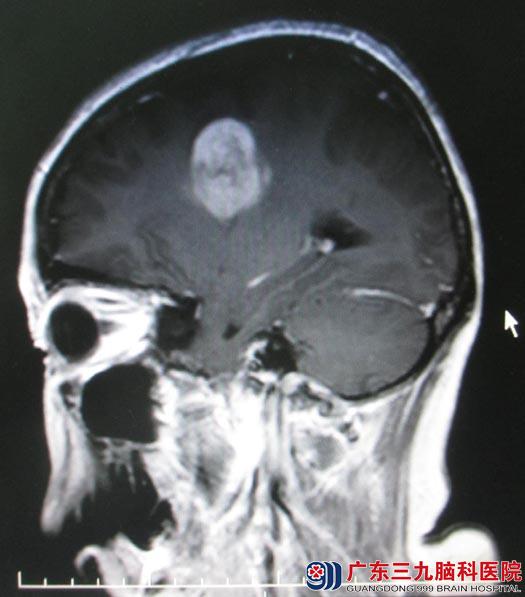

广东三九脑科医院头颅MRI检查结果:右侧顶部镰旁占位病变,呈明显高灌注,MRS支持脑外病变,内示细小血管,考虑脑膜瘤可能,待排血管外皮细胞瘤;左侧放射冠-半卵圆中心、左侧额叶多发异常信号影,局部存在多发高灌注区,NAA峰明显下降,Cho峰明显升高,SWI示病变内可见微量出血,考虑偏恶性肿瘤性病变,以间变性星形细胞瘤可能性大。

神经外五科鲁明主任阅片后解析:头颅MR所示右侧顶部镰旁占位及左侧额叶占位,右侧顶部镰旁占位考虑脑膜瘤可能,而左侧额叶占位考虑恶性肿瘤,两个肿瘤体积均较大,占位效应明显,均有手术指征,可考虑一次性手术切除。其中右顶部肿瘤侵犯上矢状窦,术中需要注意静脉窦的保护,避免静脉窦闭塞导致静脉回流障碍;左侧额叶肿瘤临近大脑语言及肢体运动中枢,术中需要注意保护正常脑组织,减少术后功能的损伤。